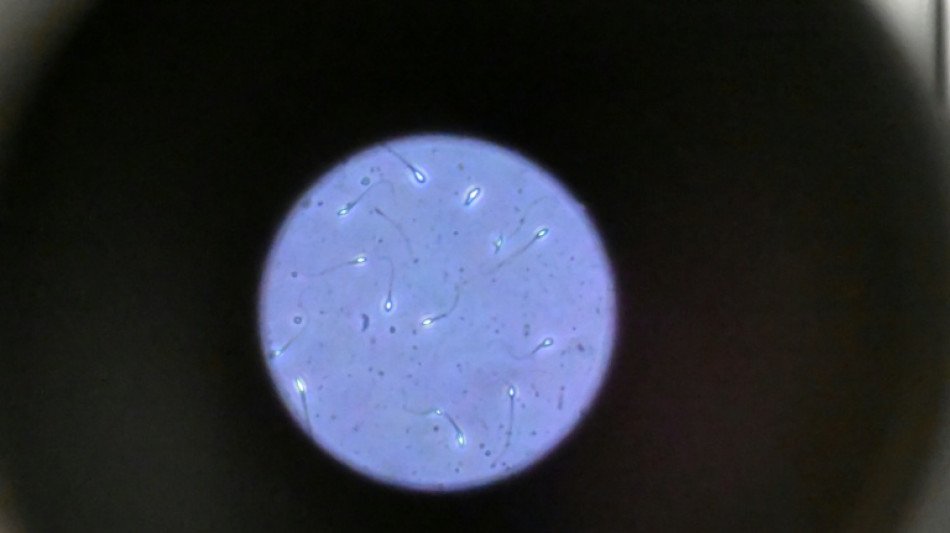

Dans l'espace, les spermatozoïdes ont du mal à trouver leur chemin / Photo: Damien MEYER - AFP/Archives

Dans l'espace, les spermatozoïdes ont du mal à trouver leur chemin vers l'ovule en raison de la microgravité, qui perturbe aussi le développement des embryons, selon une étude publiée jeudi dans Communications Biology.

"Les spermatozoïdes doivent activement trouver leur chemin vers l'ovule et cette étude est la première à tester leur capacité à le faire dans des conditions semblables à ce qui se passe dans l'espace", explique à l'AFP Nicole McPherson, autrice principale de l'étude et chercheuse à l'Université d'Adelaïde (Australie).

Son équipe a utilisé une chambre en plastique imitant l'appareil génital féminin, qui leur a servi de "parcours d'obstacles miniature". "Voyez ça comme un minuscule circuit de course... Les spermatozoïdes étaient introduits à une extrémité et devaient nager jusqu'à l'autre bout", décrit-elle.

Les chercheurs ont testé successivement du sperme de souris et humain dans ce dispositif placé dans un appareil en constante rotation pour simuler la microgravité.

Les gamètes ont été environ 50 % moins performants pour naviguer à travers ce parcours que sous la gravité terrestre. Cela équivaut à une baisse de 30% du taux de fécondation réussie, selon les résultats de l'étude.

Les spermatozoïdes ayant réussi à franchir le parcours semblaient produire des embryons de meilleure qualité.

Il semble que le stress lié à la microgravité ait agi comme un "filtre" éliminant les plus faibles et "ne laissant en lice que les plus performants", ce qui pourrait s'avérer "bénéfique", selon Mme McPherson.

Cependant, un problème plus important est apparu dans les vingt-quatre heures suivant la fécondation.

"Les résultats se sont brutalement inversés, avec moins d'embryons formés. Et ceux qui restaient étaient de moins bonne qualité", note la chercheuse.

La microgravité "n'est peut-être pas l'obstacle insurmontable que nous craignions, mais protéger les embryons de l'impesanteur au cours de ces premières heures critiques sera vraisemblablement essentiel pour la reproduction dans l'espace", avance Mme McPherson.

De nombreuses autres recherches seront cependant nécessaires pour comprendre comment la reproduction fonctionne dans l'espace, la fécondation n'étant qu'une "petite pièce d'un très grand et complexe puzzle", ajoute-t-elle. "Nous sommes encore très loin de voir un premier bébé de l'espace"!